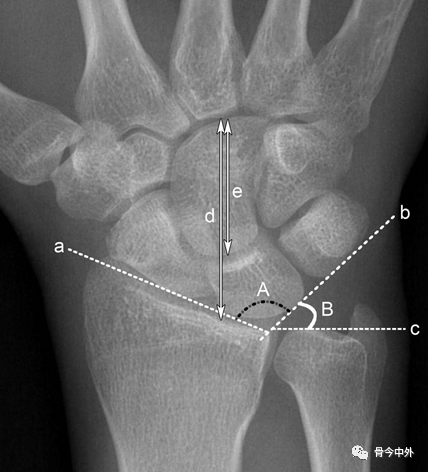

图4 a.桡骨纵轴线;b.桡骨纵轴线垂线;c.桡骨远端关节面切线;d.尺骨远端关节面水平线。A.桡骨内倾角;B.桡骨茎突长度;C.尺骨茎突长度 。

A.正常为15~35˚ 。若此角度改变,提示桡骨远端骨折或腕关节脱位。

B.正常为8~18mm,且桡骨茎突较尺骨茎突低1~1.5cm。若此长度改变,提示桡骨远端骨折。C.正常为2~8mm。若此长度改变,提示尺骨茎突骨折或尺骨茎突过长(尺骨茎突撞击综合症)

图7 a.舟骨、月骨切线;b. 月骨三角骨切线;c.尺骨远端关节面切线;d.腕骨总高度;e.头状骨长度。A.腕骨角;B.尺腕角 。

A.约130°。腕关节骨折、脱位时此角增大,此角减小见于Madelung畸形和卵巢发育不全。

B.正常为21~51˚。若此角度改变,提示腕骨骨折或腕关节脱位。

*腕骨高度指数:d与第3掌骨长度的比值,正常范围0.54±0.03。Nattrass腕骨高度指数为d/e,正常范围1.57±0.05。在月骨缺血坏死、不稳定型舟骨骨不连、腕关节不稳时,腕骨高度指数减小。